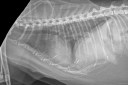

Archives du mot-clé "thorax"

Latérale du thorax